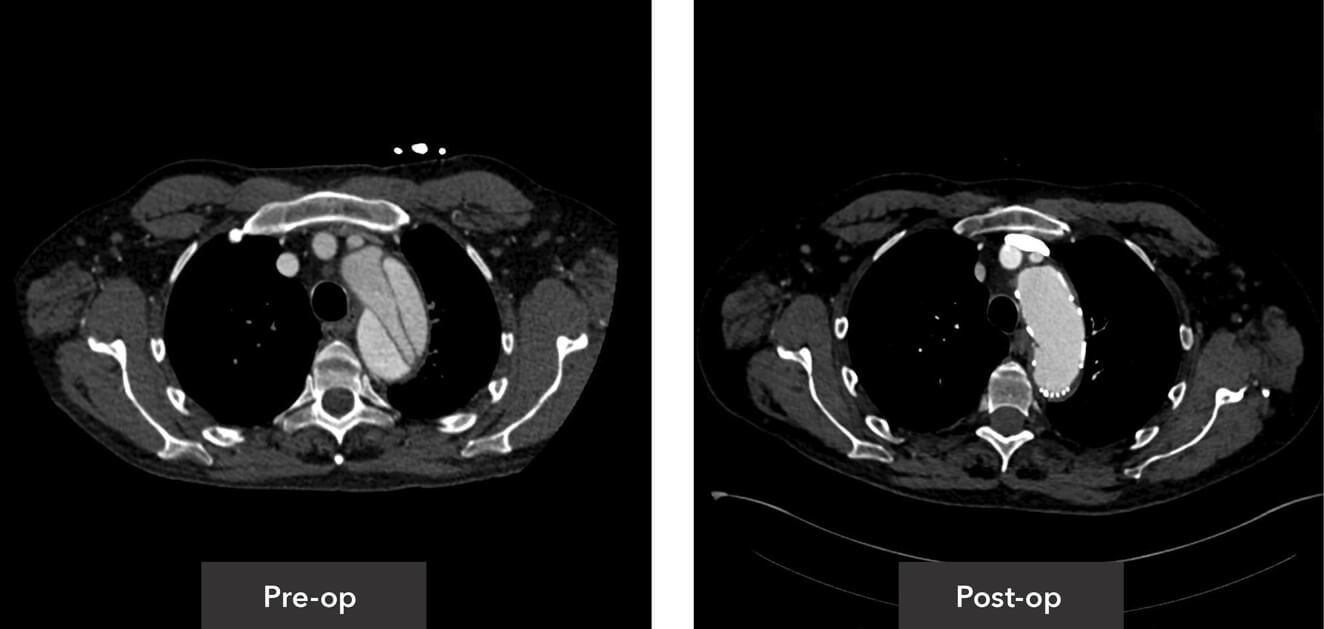

Aortic root view pre-op/post-op axial view CT imaging

Descending thoracic view pre-op/post-op axial view CT imaging